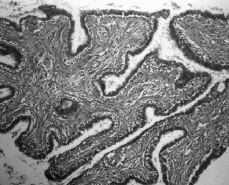

Macroscópicamente, cada una de las mamas era de configuración ovoide, de consistencia semiblanda y multinodular a la palpación. La mama derecha pesó 487 g y midió 16 x 12,5 x 5,2 cm en sus dimensiones máximas. La mama izquierda, de mayor volumen, pesó 848 g y midió 20 x 16 x 6,8 cm. La apariencia macroscópica era similar en uno y otro lado. La superficie externa era lobulada y sin restos aparentes de glándula normal. Al corte, la superficie era multinodular, alternando con cavidades de configuración variable conteniendo líquido turbio de color pardo rojizo con material mucinoso de color pardo grisáceo claro en ocasiones con tinte amarillento (Fig. 2). Los nódulos de forma esferoidal u ovoide median entre 0,3 y 4,5 cm y algunos aparecían como unidades confluentes. Después de fijación formólica se destacaron cavidades limitadas por una pared de grosor variable, repletas de un tejido con inequívoca apariencia papilar (Fig. 3). El tejido internodular era más bien escaso, de aspecto uniforme, de color gris rosado claro o blanquecino, brillante y de consistencia semiblanda. No se apreció ni necrosis, ni hemorragia, ni calcificaciones. Microscópicamente, los cambios estructurales eran similares en ambos lados. Predominaban los conductos galactóforos con grados variables de dilatación, desde la típica apariencia en «queso suizo» hasta macroquistes con más de 2 cm de diámetro (Fig. 4). La luz se encontraba ocupada por multitud de frondas papilares con ejes conjuntivos revestidos por una capa de células epiteliales cúbicas, ovoides o cilíndricas con escasa anisocariosis y mitosis aisladas. También se encontraron conductos con incremento del número de las capas de su revestimiento epitelial dando lugar a la formación de luces secundarias de configuración irregular y de distribución predominantemente periférica. No existían atipias citológicas. En algunos conductos dilatados se apreció metaplasia apocrina con pequeñas proyecciones papilares sin eje conjuntivo. Se visualizaron igualmente campos en los cuales llamó la atención una proliferación bifásica con rasgos similares a los que se aprecian en un fibroadenoma juvenil (Fig. 5). En ninguno de los múltiples planos de sección apreciamos glándula mamaria residual y el estroma entre las estructuras previamente descritas consistió en tejido conjuntivo con cantidades variables de colágeno en la matriz extracelular. El diagnóstico anatomopatológico definitivo fue de papilomatosis juvenil difusa y bilateral.

Figura 4. Aspecto microscópico a menor aumento con cambios parenquimatosos consistentes en quistes y proyecciones papilares (hematoxilina-eosina x 100).